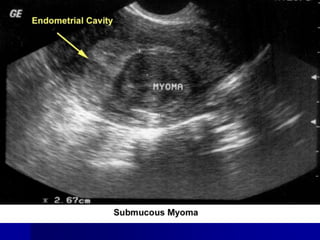

2. Ультразвукове дослідження органів малого тазу, що дозволяє

встановити розміри, кількість, локалізацію, ехогенність, структуру

вузлів, виявити наявність супутньої гіперплазії ендометрія,

5. Гістероскопія застосовується для виявлення наявності підслизових

фіброматозних вузлів, стану ендометрія, у деяких випадках –

гістеросальпінгографія. Перевагою гістероскопії є можливість

одночасної біопсії ендометрія, видалення поліпів і субмукозних

вузлів, абляції і резекції ендометрія.